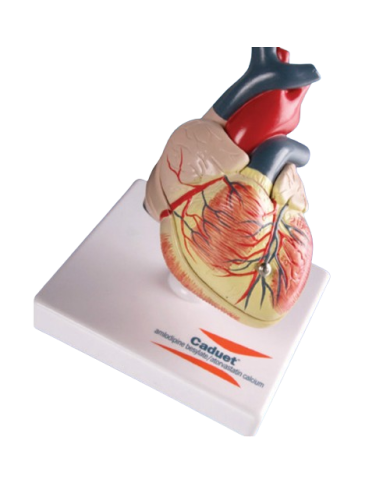

Modello anatomico PER FORNITURE CASE FARMACEUTICHE

Modello anatomico PER FORNITURE CASE FARMACEUTICHE

Modello anatomico PER FORNITURE CASE FARMACEUTICHE

Modello anatomico PER FORNITURE CASE FARMACEUTICHE

Modello anatomico PER FORNITURE CASE FARMACEUTICHE

Modello anatomico PER FORNITURE CASE FARMACEUTICHE

Modello anatomico PER FORNITURE CASE FARMACEUTICHE

Modello anatomico PER FORNITURE CASE FARMACEUTICHE

Modello anatomico PER FORNITURE CASE FARMACEUTICHE

Modello anatomico PER FORNITURE CASE FARMACEUTICHE

Modello anatomico PER FORNITURE CASE FARMACEUTICHE

Modello anatomico PER FORNITURE CASE FARMACEUTICHE

Modello anatomico PER FORNITURE CASE FARMACEUTICHE

Modello anatomico PER FORNITURE CASE FARMACEUTICHE

Modello anatomico PER FORNITURE CASE FARMACEUTICHE

Modello anatomico PER FORNITURE CASE FARMACEUTICHE

Modello anatomico PER FORNITURE CASE FARMACEUTICHE

Modello anatomico PER FORNITURE CASE FARMACEUTICHE

Modello anatomico PER FORNITURE CASE FARMACEUTICHE

Modello anatomico PER FORNITURE CASE FARMACEUTICHE

Modello anatomico PER FORNITURE CASE FARMACEUTICHE

Modello anatomico PER FORNITURE CASE FARMACEUTICHE